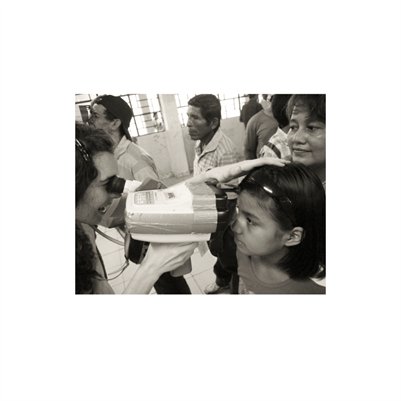

Darkness into the Light. In 2012, The Amazon Project gave eye care to nearly 6000 patients within a 200 kilometer radius of their base in Leticia, Colombia.